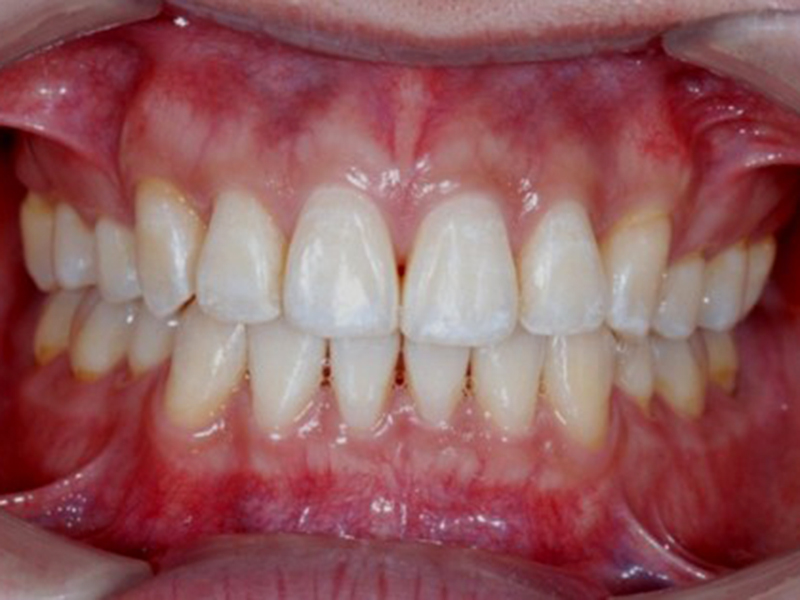

after